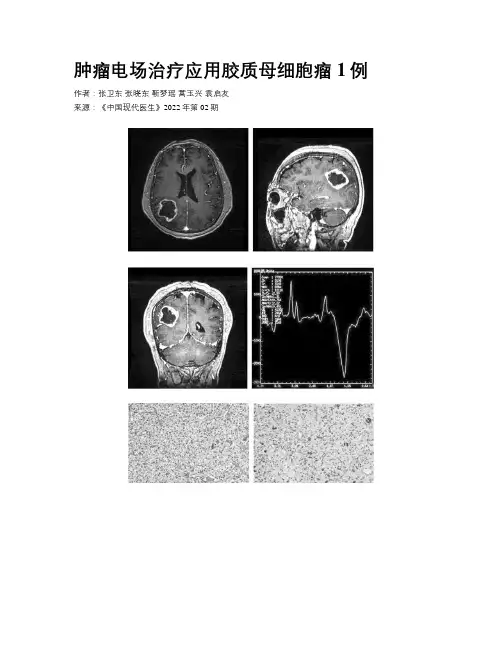

肿瘤电场治疗应用胶质母细胞瘤1例作者:张卫东张晓东靳梦瑶蒿玉兴袁启友来源:《中国现代医生》2022年第02期[摘要] 胶质母细胞瘤(GBM)是成人最常见的原发性恶性肿瘤,在星形细胞肿瘤中恶性程度最高,手术合并放化疗是GBM标准的治疗方式。

由于其浸润性,肿瘤无法完全切除,胶质母细胞瘤容易复发且预后较差,因此需要寻求更有效的治疗方法,其中肿瘤电场治疗(TTFields)与放化疗联合治疗方案显著延长了胶质母细胞瘤的生存时间。

本文报道1例GBM患者,手术切除肿瘤后行规律放化疗同步TTFields治疗,现患者预后良好,术后复查MRI未见肿瘤复发。

[关键词] 胶质母细胞瘤;手术;放射治疗;化学治疗;肿瘤电场治疗[中图分类号] R739.4 [文献标识码] C [文章编号] 1673-9701(2022)02-0145-03A case of glioblastoma combined with Tumor Treating FieldsZHANG Weidong ZHANG Xiaodong JIN Mengyao HAO Yuxing YUAN QiyouDepartment of Neurosurgery, the First Affiliated Hospital of Anhui Medical University,Hefei 230000, China[Abstract] Glioblastoma (GBM) is the most common primary malignant tumor in adults. It is the most malignant among astrocytic tumors. Surgery combined with radiotherapy and chemotherapy is the standard treatment for GBM. Due to its invasiveness, the tumor cannot be completely removed, and glioblastoma is prone to relapse and has a poor prognosis. Therefore, we need to seek more effective treatment methods. Among them, Tumor Treating Fields(TTFields)combined with radiotherapy and chemotherapy significantly prolongs the glial Survival time of blastoma. This article reports a case of GBM patient who underwent regular radiotherapy and chemotherapy and concurrent TTFields treatment after surgical resection of the tumor. The prognosis of the patient is good, and there is no tumor recurrence in the postoperative MRI.[Key words] Glioblastoma; Operation; Radiotherapy; Chemotherapy; Tumor treating fields膠质母细胞瘤(glioblastoma,GBM)在原发性脑恶性肿瘤中占45.6%,GBM的发病率与年龄相关,随着年龄的增长,儿童的发病率为0.15/100 000,到75~84岁老年人的发病率达到峰值,为15.03/100 000[1]。